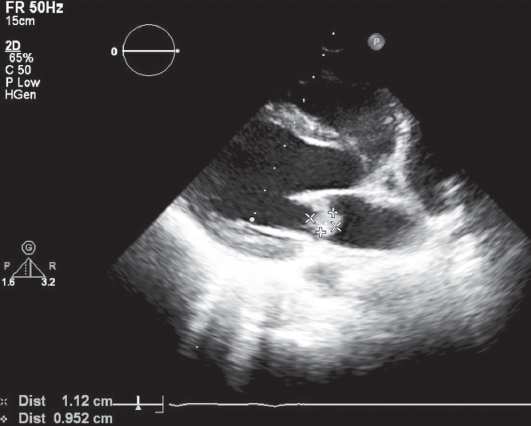

Оптимальные сроки операции на клапанах сердца у пациентов с активным инфекционным эндокардитом (ИЭ) до сих пор остаются спорными. Общеизвестно, что наиболее частой причиной смерти больных с левосторонним ИЭ является системная тромбоэмболия, поражающая церебральные, коронарные или почечные сосуды, которая может развиться еще до появления клинических проявлений поражения клапанного аппарата сердца. В настоящее время раннее хирургическое вмешательство рассматривается как наиболее эффективный метод лечения большинства форм активного ИЭ с поражением левых отделов сердца, которое подразумевает под собой выполнение хирургической коррекции еще до завершения полного терапевтического курса антибиотиков. Представляется клинический случай раннего успешного хирургического лечения инфекционного эндокардита митрального клапана (МК) у пациентки А., 16 лет. Заболевание протекало остро, с рецидивирующими эмболиями, повлекшими за собой инфаркт правой почки, а также остеомиелит левой ключицы. Хирургическое вмешательство производилось в срочном порядке из правосторонней переднебоковой торакотомии. Операция была проведена на 4-е сутки от момента госпитализации в кардиохирургический стационар. Однако потеря времени на догоспитальном этапе лечения, стремительное развитие грубых деструктивных изменений на МК, к сожалению, не позволили выполнить реконструктивное вмешательство. Произведено протезирование МК. Течение послеоперационного периода гладкое, на 3 сутки девочка была переведена в общесоматическое отделение. При контрольной эхокардиографии через 3 года сократительная функция миокарда сохранена, фракция выброса 65 %, функция протеза не нарушена.